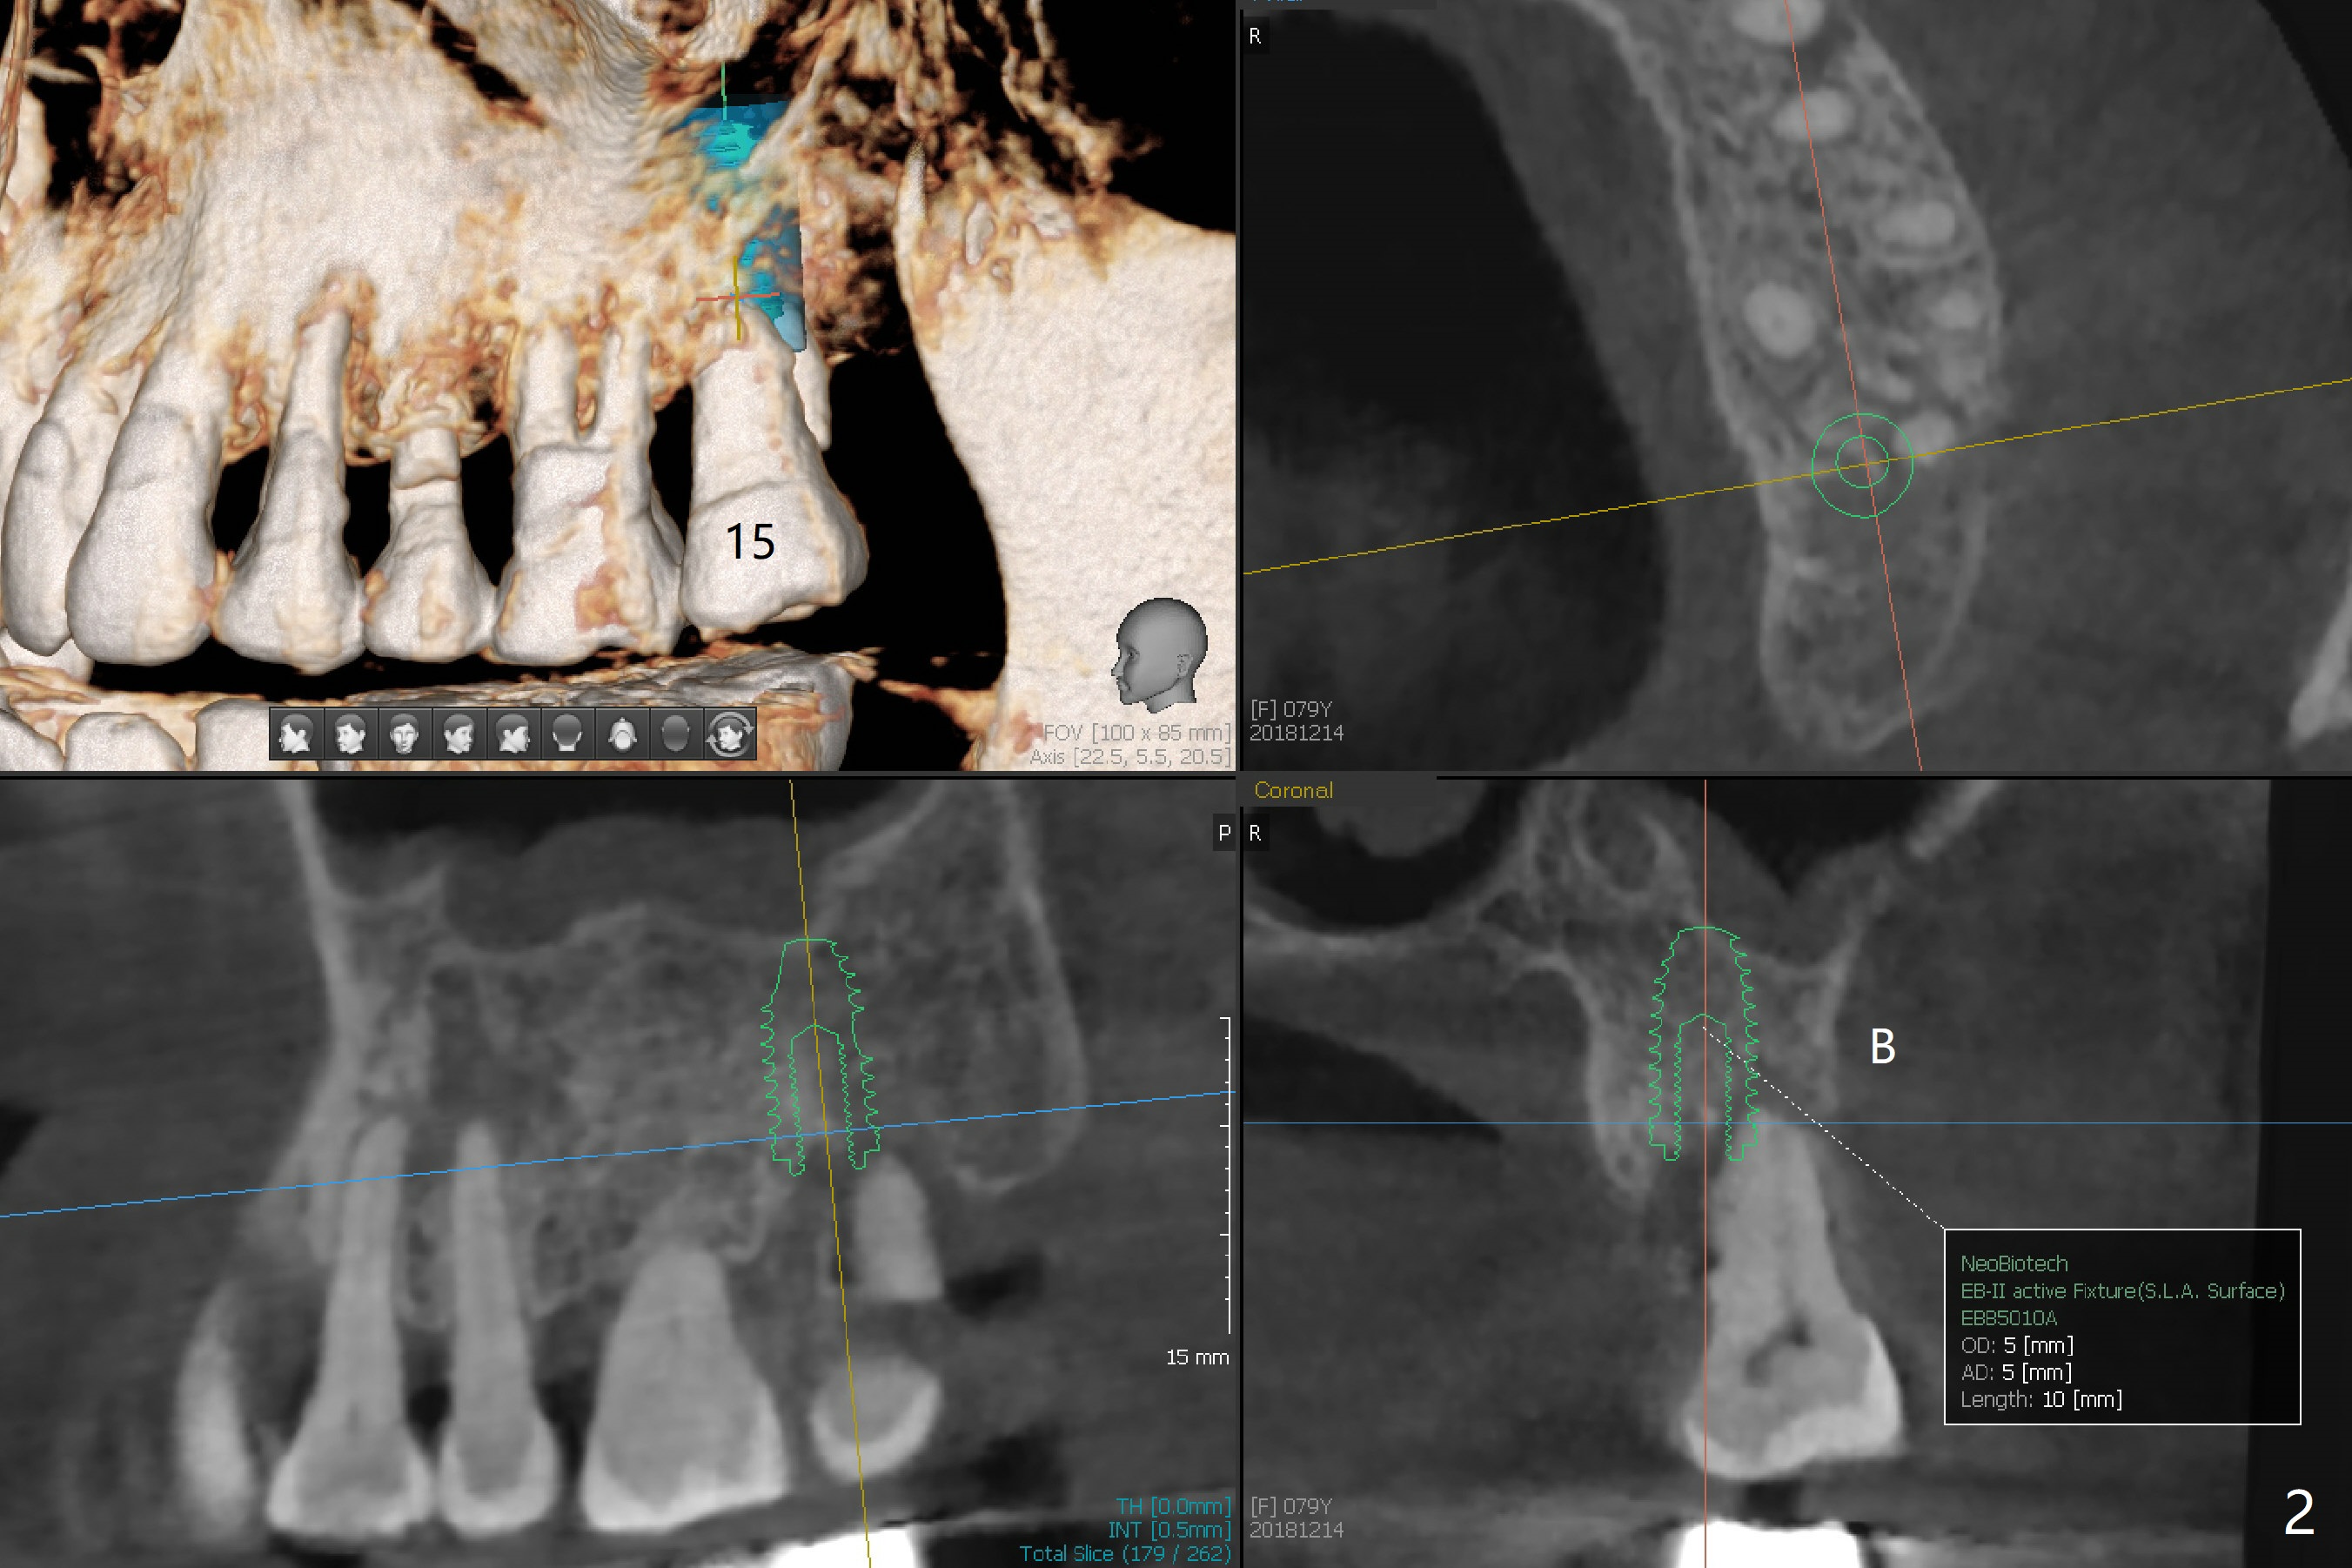

A 79-year-old woman returns to clinic suddenly, requesting extraction of the tooth #31 with mobility III (3 years 8 months post cementation for #25; 2 years 6 months post cementation for #18-20; Fig.4). An immediate implant is planned (Fig.1). After extraction, the large socket has relatively small opening, seemingly easy to keep bone graft in place. The immediate implant with 2-3 mm native bone may not have primary stability, most likely losing its ability to hold bone graft. Therefore socket preservation is conducted at #31. In contrast there is enough bone for an immediate implant at #15 (Fig.2) with palatal root fracture (Fig.3 (palatal view)).